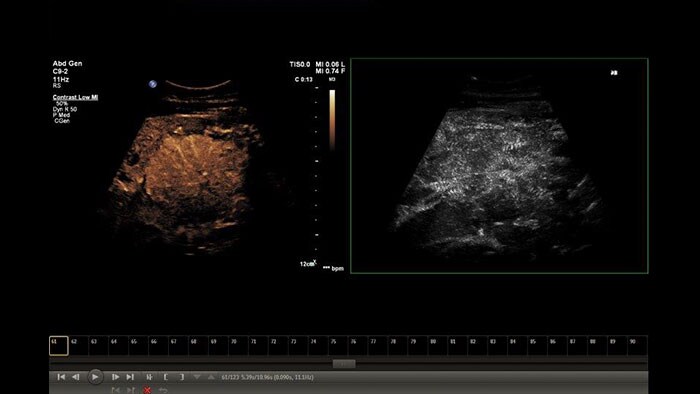

Perform advanced analysis of 2D, Color and CEUS data

The Q-App Region of Interest (ROI) provides dedicated tools for spatial and temporal analysis of regions of interest in 2D, color and contrast enhanced* ultrasound exams (CEUS). This Q-App also provides basic 2D measurement tools (distance, area) as well. For CEUS applications, multiple motion compensated regions can be defined for contrast bubble analysis to generate wash-in/wash-out curves for lesion blood flow assessment.

Benefits

*Ultrasound contrast agents are approved for use in Left Ventricular Opacification (LVO), focal Liver lesions characterization, and for the evaluation of suspected or known vesicoureteral reflux in pediatric patients’ urinary tract ultrasonography.